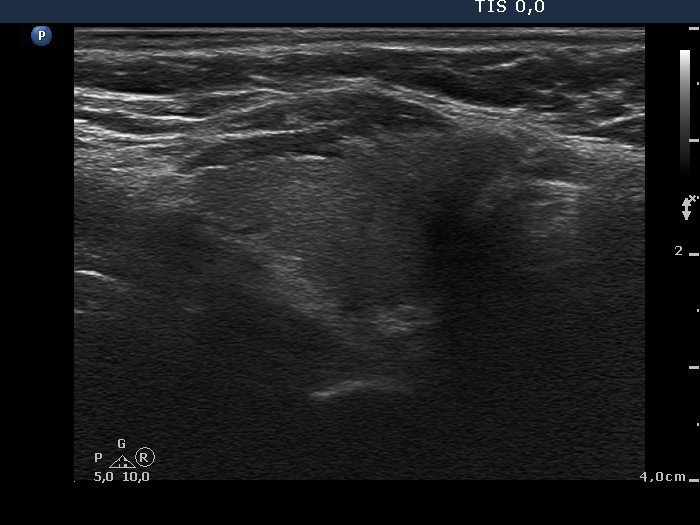

Ultrasound. The thyroid was minimally-moderately hypoechogenic. There was an echonormal lesion in the ventral part of the left lobe. The dimensions were 11x10x15 mm. The lesion had a geometrical shape, sharp borders and presented signs of perinodular blood flow. The lesion is probably a true nodule.